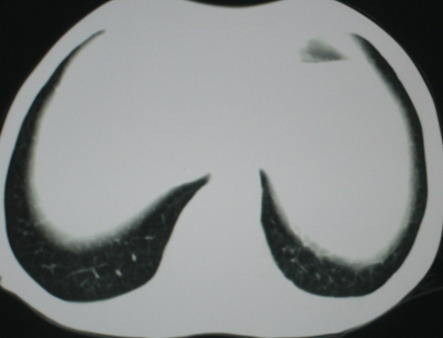

以下是引用医影拾贝在2008-6-3 18:48:00的发言:[br]双上肺弥漫性小结节影,纵隔窗内钙化淋巴结影,考虑血播性tb可能性较大,不除外肺ca可能

以下是引用卜一在2008-6-3 19:33:00的发言:[br]双肺结节,以双上肺分布为多,期间搀杂片状致密影及索条致密影。考虑:继发性肺结核伴血型播散可能性大。不除外肺泡ca的可能!另:椎体退变!

以下是引用panyishengct在2008-6-3 21:09:00的发言:[br]双上肺弥漫性小结节影,纵隔窗内钙化淋巴结影,考虑矽肺或/和tb可能性较大,不除外肺ca可能。腰椎考虑退变。 [br][br]